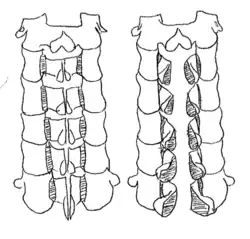

Double door laminoplasty

At the midline of the vertebral laminae, a drill is used to cut the bone. The lateral sides of the laminae serve as a hinge that allows expansion of the spinal canal. Specifically, the inner cortex of the lateral portion was part of the hinge. An artificial spacer is used to keep the opening fixed. One common spacer that is used is hydroxyapatite.[1]